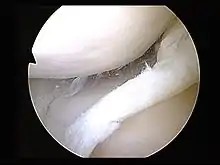

الجراحة

التنظير المفصلي هو طريقة جراحيَّة، حيث يتم العمل على المفصل باستخدام آلة تصوير تنظيريَّة صغيرة بعكس الجراحة المفتوحة على المفصل، ويمكن إصلاح الغضروف الهلالي أو إزالته بالكامل، وهذا موصوف بشكل مفصل أكثر في الأسفل،[13] ولا يجب التوصية بهذه الطريقة في حالة تمزق المفصل الهلالي الانحلالي إلا إذا كان هناك قفل أو غلق في الركبة أو ارتشاح و ألم متكرران،[14]، إلا أن الأدلة تدعم عدم كونه أفضل من التدبير التحفظُّي في المصابين بالالتهاب المفصلي العظمي[17] بالإضافة إلى ذلك فيظهر أنه ليس هناك أي منفعة في البالغين المصابين بتمزق الغضروف الهلالي مع التهاب مفصلي.[17] . إذا فشل شخص بالتحسن بعد محاولة هذه العلاجات، فيجب التفكير باستخدام التنظير المفصلي، والمرضى الذين لديهم بالإضافة إلى ذلك التهاب مفصلي عظمي قد يحتاجون خيارات جراحيَّة.[14]

إذا كانت إصابة الغضروف الهلالي معزولة، فتكون الركبة مستقرة نسبيًّا، ولكن إن كان تمزق الغضروف المفصلي مقُترنًا بإصابة أخرى كإصابة الرباط الصليبي الأمامي، فيتم استخدام التنظير المفصلي، ويمتلك إصلاح تمزق الغضروف الهلالي نسبة نجاح أعلى إذا كان يمتلك إمدادات دمويَّة كافية لحافته الطرفيَّة،[18] فالجزء الداخلي من الغضروف الهلالي لا وعائي، ولكن إمدادات الدم تستطيع أن تخترق حوالي 6 ميليلترات أو ربع إنش منه، لذلك فإن التمزقات الغضروفيَّة الهلاليَّة التي تحدث قرب الحافة الطرفيَّة تُشفى بعد إصلاح الغضروف الهلالي، وقد وجدت دراسة قام بها باربر- ويستن ونوياس أنه من الأفضل إصلاح الغضروف الهلالي بدلًا من إزالته بالكامل (استئصال الغضروف الهلالي).